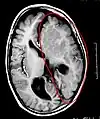

Cerebro enfermo, antes de la hemisferectomía